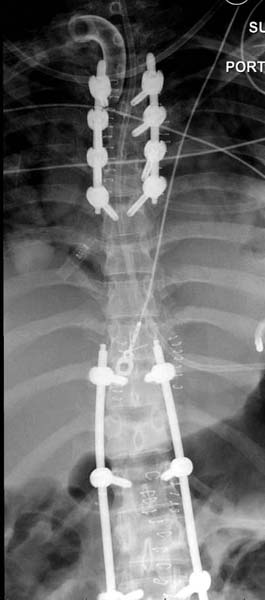

> Остеосинтез бедра не стали делать из-за множественных переломов ребер с

> ушибом грудной клетки и поэтом у закончили фиксацию бедра наружным

> фиксатором.

> Около 11.00 вечера больная переведена в реанимацию, без сознания, но

> стабильная.. На третьий день провели стабилизацию перелома бедра

> антеградным остеосинтезом.

> Закрытый БИОС решает множественные проблемы связанные с лечением

> переломов, но проблема дистальной блокировки без рентгена до сих пор

> остается нерешенной. Рекламированные производителями приспособления для

> дистальной блокировки из-за различной кривизны кости не эффективны или

> стоит очень дорого (Smith&Nephew SureLock). Задержка операции из-за

> блокировки не всегда удовлетворяет, и многих вынуждает искать

> альтернативные методы фиксации. С результатами таких действий,

> остеомиелитом и несращениями, встречаемся в ежедневной жизни..